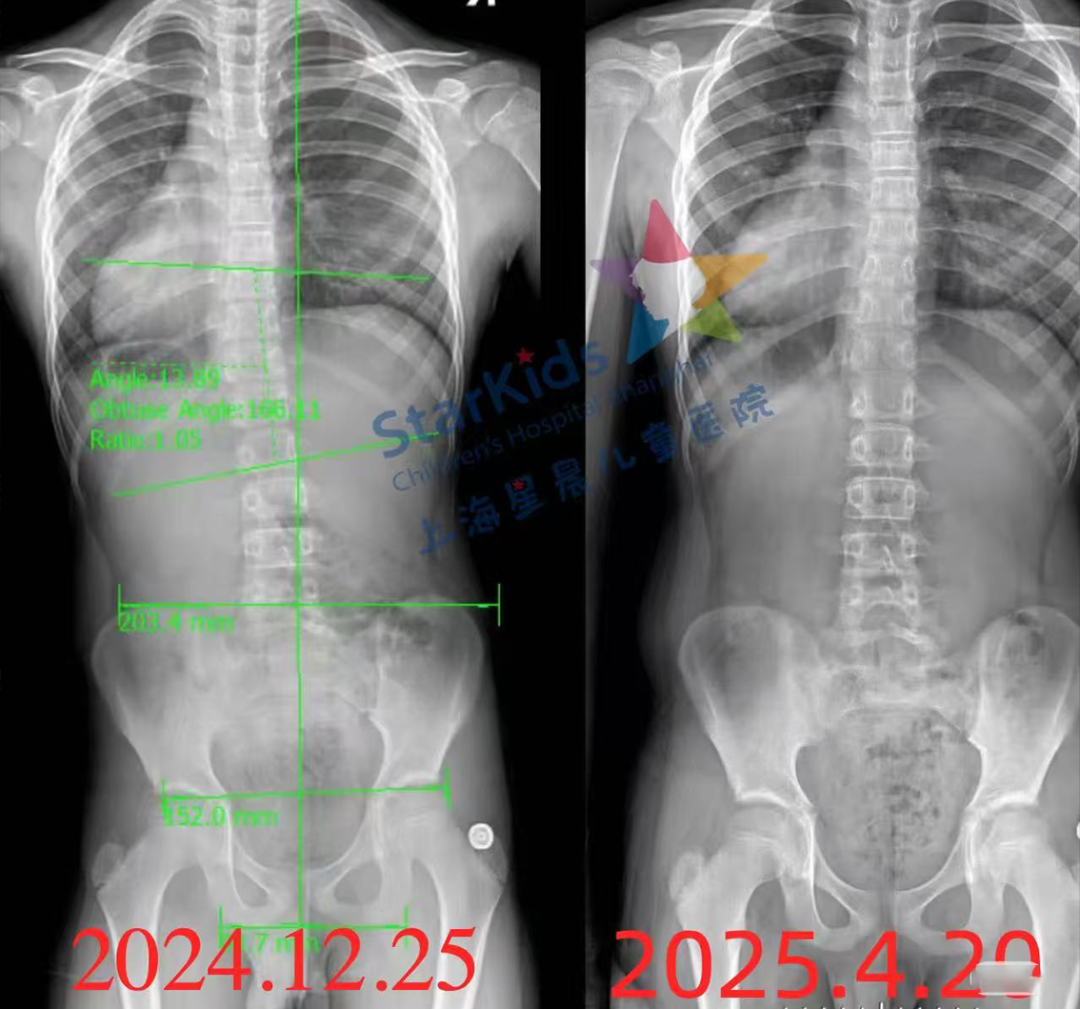

专业诊断:专家解读全脊柱X光片 + 步态生物力学分析

上海星晨儿童医院

暨复旦大学附属儿科医院新虹桥分院